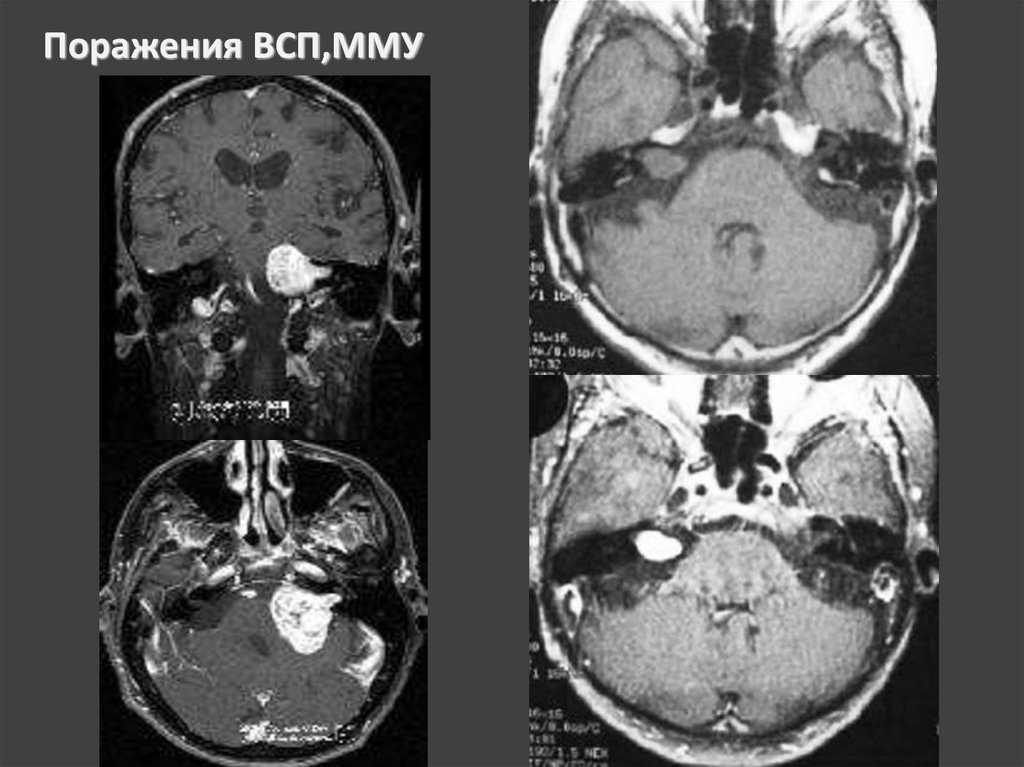

Поражения ВСП,ММУ

НЕВРИНОМА

Наиболее частые опухоли ММУ

Доброкачественная опухоль из шванновских клеток

Растет экзофитно

Поражает 8, реже 5, еще реже 9,10,11 ЧМН

В 90% односторонние, двустороннее поражение

подозрительно на НФМ II типа

рентгенография в проекции Стенверса –

-расширение внутр. слухового прохода,

-изменение его формы (чаще отмечается веретенообразность)

-изменение корт/ слоя кости, ограничивающего просвет прохода —

появление эррозий, узур, стертости контура

-асимметричность изображения поперечного гребня в области дна

прохода.

Участки атрофии костной ткани при невриномах имеют гладкие и четкие

очертания.

НЕВРИНОМА СЛУХОВОГО НЕРВА

КТ — признаками опухоли слухового нерва являются:

расширение слухового прохода, наличие округлого, реже

овального объемного образования, зачастую с очагами

кистозной дегенерации и хорошей реакцией на усиление,

острый угол между поверхностью опухоли и задней

поверхностью височной кости

ВСП шире 8 мм,

асимметрия >2 мм

подозрительны